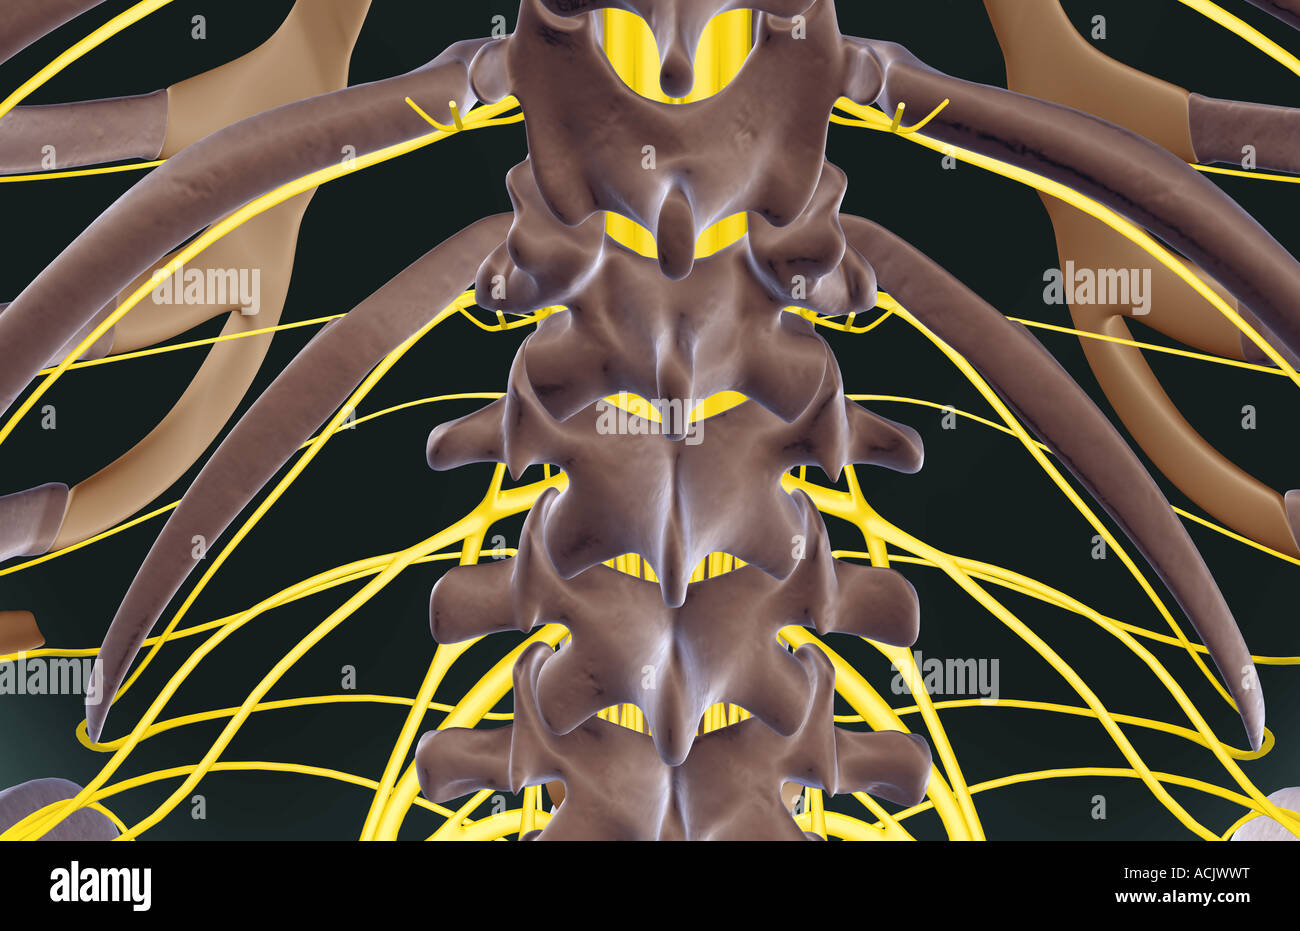

From www.alamy.com

The lumbar and sacral plexus Stock Photo Alamy Lumbar Plexus Images Mrn images in coronal stir 3d space (c) demonstrate lumbar plexus trunk thickening (arrowhead). The lumbar plexus gives rise to several branches which supply various muscles and regions of the posterior abdominal wall and lower. The lumbar plexus is a complex neural network formed by the lower thoracic and lumbar ventral nerve roots (t12 to l5) which supplies. Use them. Lumbar Plexus Images.

Lumbar plexus Stock Photo 69117762 Alamy Lumbar Plexus Images The lumbar plexus gives rise to several branches which supply various muscles and regions of the posterior abdominal wall and lower. Schematic of the lumbar plexus. An image of the lumbar plexus with its nerves highlighted in yellow. Mrn images in axial t2. Use them in multiple choice question; Creating your own cases is easy. Mrn images in coronal stir. Lumbar Plexus Images.